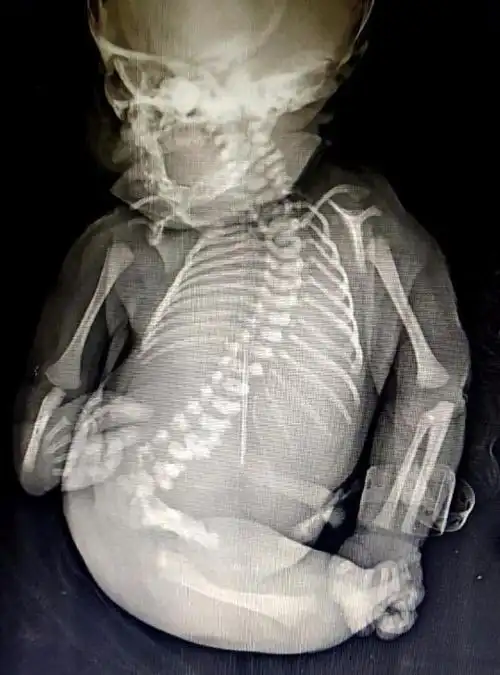

羊膜带导致新生儿左手手指部分畸形